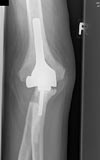

​Die Gonarthrose bezeichnet die Abnutzung des Kniegelenkes. Klinische Zeichen sind auch hier Schmerzen und Bewegungseinschränkungen sowie eventuell eine fortschreitende Fehlform des Beines (O-Bein, X-Bein). Der Gelenkersatz wird als Knietotalendoprothese (KTEP) bezeichnet.

Hier werden die Gelenkflächen von Oberschenkelknochen (Femur) und Schienbein (Tibia) ersetzt. Zwischen die beiden Gelenkteile aus einer Metalllegierung wird ein Plastikinlay eingefügt, um eine adäquate Beweglichkeit zu gewähren. Wir verwenden in unserer Klinik in erster Linie Knieendoprothesensysteme der Firma DePuy (LCS Complete und LCS Complete Revision)

Gonarthrose Knietotalendoprothese Röntgenbild KTEP